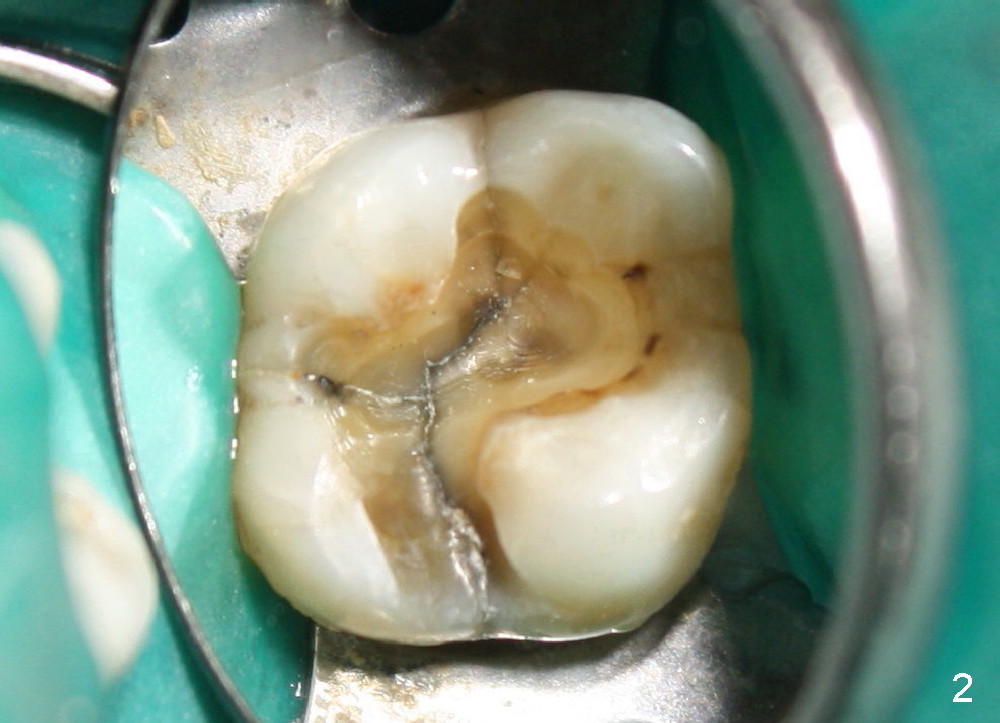

A 49-year-old lady has toothache at the upper left 1st molar (Fig.1).  Removal of the occlusal amalgam reveals crack lines (Fig.2).  After atraumatic extraction (sectioning), osteotomes are used to form osteotomy in the septum (Fig.3 S).  Finally the osteotomy seems to drop into the palatal socket.  No bone graft is used.  The socket is closed by elavating the buccal flap (Fig.3) and severing the periosteum.  Periodontal dressing is applied for wound protection (Fig.4 P). Is the implant in the sinus (S)?